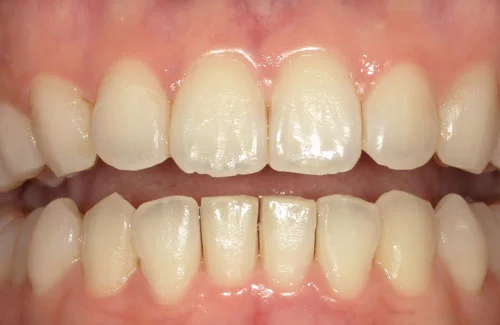

<症例5>上の前歯が飛び出しているお悩み

下の歯のガタガタと若干の前歯のズレの矯正でした。

アーチが綺麗に揃ったことにより見た目が改善されたほか、ステインや歯石も付きにくくなりました。

患者様と症状

主訴:下の歯がガタガタ

性別・年齢:20代女性

問題点:叢生、ディープバイト

診断:前歯部の叢生を伴うアングルⅠ級の不正咬合

主なリスク:矯正中一時的に咬合しにくくなる、歯肉退縮

症状:叢生(そうせい) 過蓋咬合(かがいこうごう)

治療内容

治療期間:3ヶ月

治療費用:330,000円(税込)

プラン:8枚コース/アーリープラン

抜歯:無し

再診治療費:無し

追加治療費:無し

保定装置費:無し

治療前後の写真